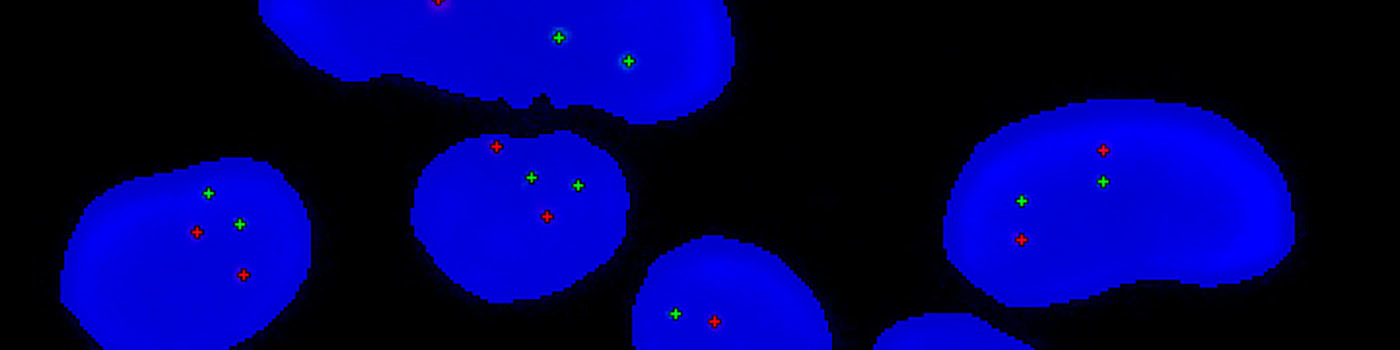

Close-up of a group of nuclei including gene probes.

To determine the HER2/CEN-17 ratio, the total number of HER2 signals (Red) and the number of CEN-17 (Green) signals in the same 20 nuclei are identified. The total number of HER2 signals is then divided by the number of CEN-17 signals. Ratios above 2 are classified as amplified whereas ratios below 2 are classified un-amplified. Caution should be taken when intepreting on results near the cut-off (1.8 – 2.2). The operator only needs to define an overall region of interest.

The image analysis algorithm for this protocol involves several steps. First, a pre-processing step identifies the stained nuclei and the gene probes. Nuclei exhibiting signals of only one color are then removed.